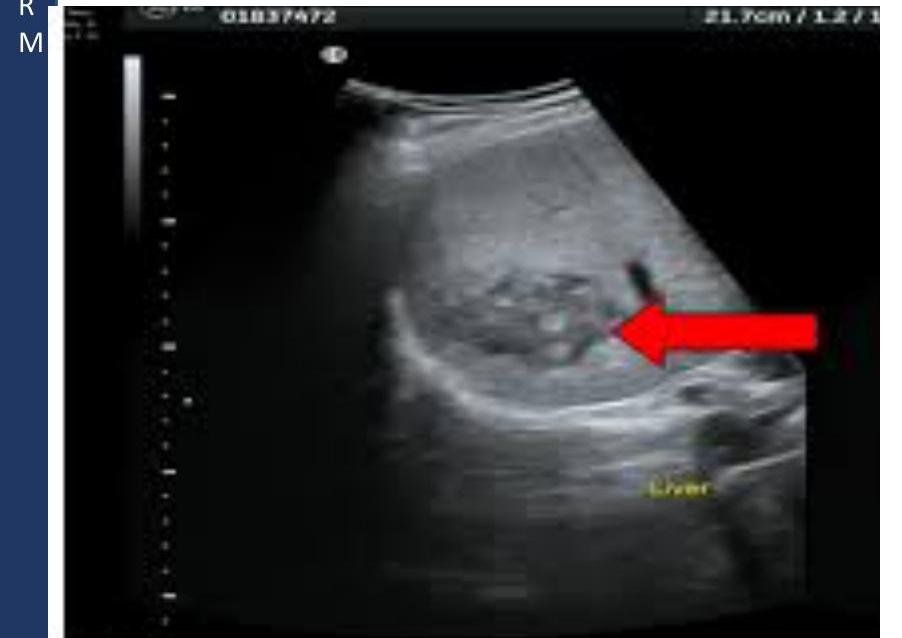

# ABSCESO HEPÁTICO ## DEFINICIÓN Es una necrosis enzimática de los hepatocitos y múltiples microabscesos que confluyen, formando habitualmente cavidad única, conteniendo líquido homogéneo que puede variar en color, desde la crema blanca hasta el de "pasta de anchoas". ## ABSCESO HEPÁTICO AMEBIANO Es la manifestación extraintestinal más frecuente de la infección por *Entamoeba histolytica*. Causada por la ingesta de quistes en el agua o alimentos contaminados. Pudiendo tener antecedente de **disentería amebiana**. ## ABSCESO HEPÁTICO PIÓGENO Es el absceso hepático más frecuente de etiología por colangitis ascendente, criptogénico, vía portal o arterial por algún **foco séptico**, por contigüidad (colecistitis o peritonitis). ## EPIDEMIOLOGÍA - La amebiasis es la segunda causa de muerte por enfermedad parasitaria en todo el mundo. - El parásito causante es un patógeno potente, posee proteasas secretoras que disuelven los tejidos del huésped, matando por contacto a las células y fagocitando a los eritrocitos. | FACTORES DE RIESGO AMEBIANO | FACTORES DE RIESGO PIÓGENO | | :------------------------------------------------------------------------------------------------------------------------ | :----------------------------------- | | - Sexo masculino - 3^{\circ} a 5^{\circ} década de la vida - Alcoholismo - Padecimientos oncológicos - Prácticas homosexuales - Inmunosupresión - Habitar o viajar a **zonas endémicas** - Uso de corticosteroides | - Presencia de **foco infeccioso** - Mayores de 50 años | # CLÍNICA | ABSCESO AMEBIANO | ABSCESO PIÓGENO | | :------------------------------------------------------------------------------------------------------------- | :----------------------------------------------------------------------------------------- | | - Fiebre vespertina o nocturna no muy alta. - Dolor en hipocondrio derecho - Hepatomegalia - **Ictericia** - Escalofríos y malestar general. (puede haber antecedente de disentería) - **Amebomas**: masas ileocecales en CSD | - Fiebre aguda en picos - Dolor en hipocondrio derecho - **Ictericia** - Vómitos - Anorexia - Mialgias y malestar general (puede haber **choque séptico**) | ## DIAGNÓSTICO ## GOLD STANDARD: USG DE HÍGADO Y VÍAS BILIARES - Es el estudio de elección ante la sospecha de un absceso hepático de cualquiera de sus etiologías. - Colección única en **lóbulo hepático derecho** sugiere origen amebiano (80%). ## PUNCIÓN GUIADA POR USG O TAC - Se realiza cultivo del aspirado del absceso para llegar a un diagnóstico etiológico definitivo.   # TRATAMIENTO ## ABSCESO AMEBIANO ## 1ª elección: **Metronidazol + Amebicida intraluminal** (Furoato de Diloxanida, Paromomicina). ## 2ª elección: Si hay intolerancia a Metronidazol - **Tinidazol**. Si hay intolerancia a Imidazoles - **Nitazoxanida**. ## PUNCIÓN PERCUTÁNEA - Persistencia de síntomas clínicos de 72 horas de iniciado el tratamiento. - Datos de **ruptura inminente**. - Absceso de **lóbulo hepático izquierdo**. - Embarazo y contraindicación del uso de Metronidazol. - Complicaciones pleuropulmonares (absceso que se va a pleura). ## ABORDAJE LAPAROSCÓPICO - Drenaje por esta vía si hay **fracaso** en el percutáneo. ABORDAJE LAPAROTOMÍA - En caso de **ruptura** del absceso a cavidad peritoneal. ## ABSCESO PIÓGENO 1ª elección: **Antibiótico de amplio espectro + Drenaje percutáneo**. Esto debe indicarse en **TODOS** los casos. Elegir el antibiótico con base en la etiología más frecuente del foco séptico responsable. El drenaje percutáneo también deberá servir para descomprimir la vía biliar. ## DRENAJE QUIRÚRGICO - Absceso **múltiple**. - **Multiloculado**. - **Foco infeccioso** que requiere cirugía. - Si el drenaje no es posible por su localización (**superior o posterior**). # PRONÓSTICO ## MORTALIDAD | ABSCESO AMEBIANO | ABSCESO PIÓGENO | | :------------------------------------------------- | :-------------- | | 1 % | 20 % | | Complicación más frecuente - **Lesión pleuropulmonar**. | | ## FACTORES DE MAL PRONÓSTICO - Abscesos **múltiples**. - Volumen **>500 ml**. - Elevación del **hemidiafragma derecho** (o derrame pleural). - **Encefalopatía**. - Bilirrubina **>3.5 mg/dL**. - Hemoglobina **<8 mg/dL**. - Albúmina **<2 g/dL**. - **Diabetes mellitus**. ## REFERENCIA Enviar a **segundo nivel** si hay sospecha de absceso amebiano.